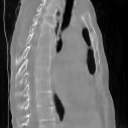

The results presented in Table 1 and 2 show our proposed method’s performance on unconditional 3D brain MR and chest CT image generation. Our proposed approach not only outperforms most comparing methods in FID and MS-SSIM metrics, it also has the lowest inference GPU memory footprint at a resolution of and was the only diffusion-based method that could be trained at a resolution of . Operating in the wavelet domain and profiting from the reduced spatial dimension also results in a relatively short inference time of / at the respective resolutions. Compared to the results presented in [23], we did not find that incorporating wavelet information into the network’s feature space (WavU-Net) increased the model’s performance. Qualitative results of our proposed method (WDM) are shown in Fig. 2 and 3. A qualitative comparison of samples produced by all evaluated methods can be found in the Supplementary Material.